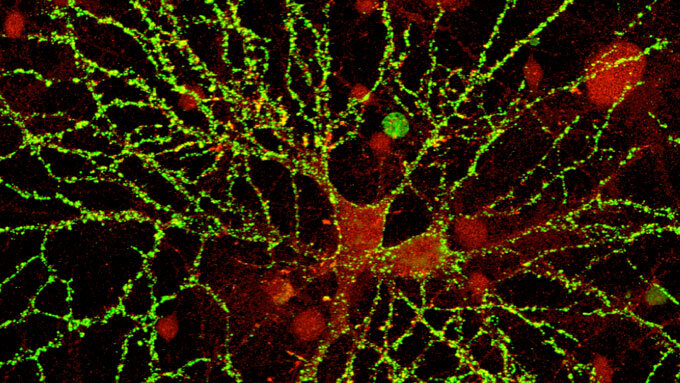

• оливковое масло первого отжима, источник витамина К, необходимый для увеличение костной массы и защиты нейронов головного мозга;

Масло оливковое extra virgin действует на человека как нестероидные противовоспалительные средства ибупрофен или парацетамол, помогает подавлять неспецифические хронические воспаления, а олеакантал (антиоксидантное соединение, найденное в оливковом масле способно убивать онкоклетки менее чем за час, оставляя здоровые клетки невредимыми. Это подтверждается данными исследования, проведенного учеными из Рутгерского Университета и Хантер Колледжа, которое опубликовано в журнале Molecular & Cellular Oncology) снижает С-реактивный белок (воспалительный маркер) и предупреждает нежелательное свёртывание крови, защищая сердце от инфаркта и мозг от инсульта.